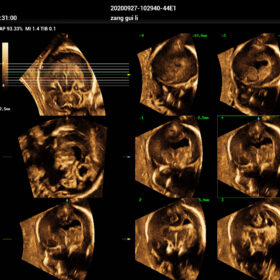

- Smart Scene 3D – Full Stack smartness obstetric solution empowered by ZST+. Comprehensive 3D/4D OB imaging solution with comprehensive fetal parts coverage.

One Key for favorite fetal part imaging, reducing manual adjustment - Smart Face – Automatic removal of occlussions over fetal face with one click

- Smart OB – Accurate auto measurements of most frequently examined parameters BPD/HC/FL/AC/OFD with a single click